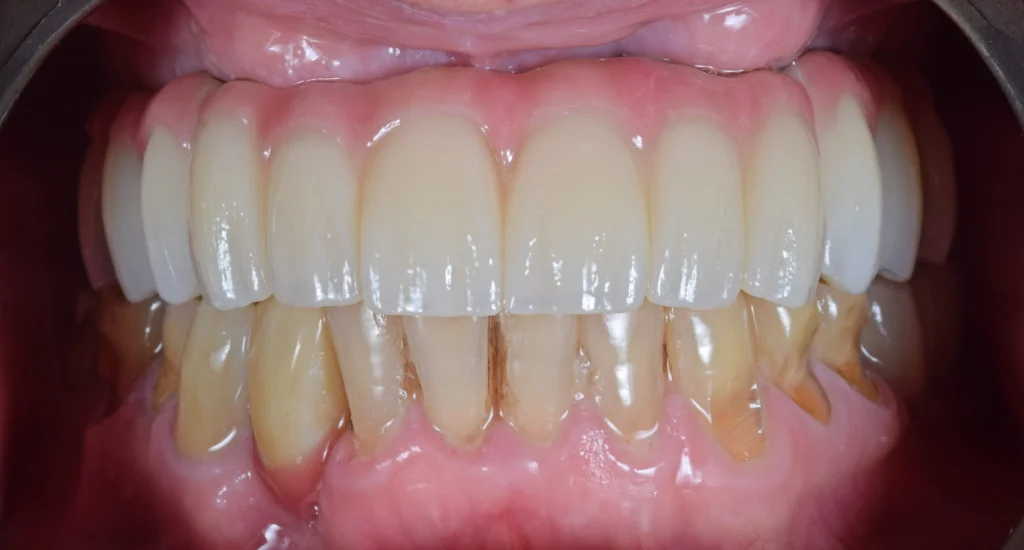

After 5 months of healing the implants were integrated in the bone and we provided the patient with his final teeth. A hybrid construction with titanium and zirconia was made. A functional, healthy and natural smile was achieved.

This kind of cases show us that using digital workflows in implant therapy makes our job more predictable and our life easier.Â